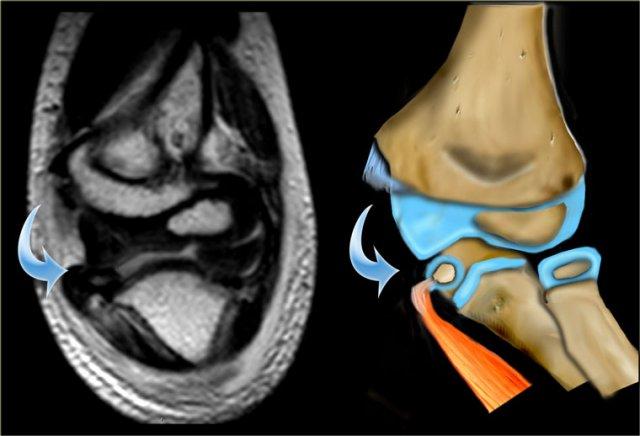

MR of lateral condyle fracture. Milch II and unstable elbow. T2 image with fat saturation on the right shows cartilaginous fracture. Fracture-fragment surrounded by synovial fluid. (Courtesy of Lynne Steinbach, M.D. Univ. of California, San Francisco)

MRI có thể hữu ích trong việc mô tả toàn bộ phạm vi của thành phần sụn trong gãy xương.

Trường hợp bên trái cho thấy đường gãy xương kéo dài vào gờ ròng rọc chưa cốt hóa.

Đường gãy qua sụn ròng rọc nằm xa về phía trong đến mức xương trụ chỉ được đỡ ở phía trong.

Điều này có nghĩa là khớp khuỷu tay không ổn định.

Continue with the MRI.

MRI cho thấy mỏm trên lồi cầu trong nhỏ cùng với điểm bám gân bị kẹt trong khớp.

Mỏm trên lồi cầu trong bị bật ra được tìm thấy trong khớp và được định vị lại, cố định bằng dây Kirschner.